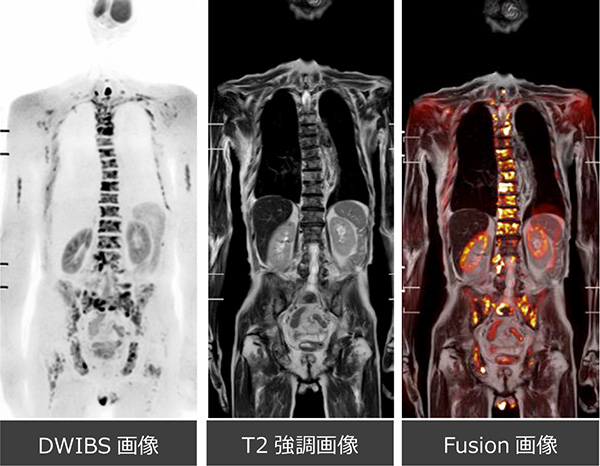

全身の拡散強調mri画像 前立腺がん 東京医科歯科大学大学院医歯学